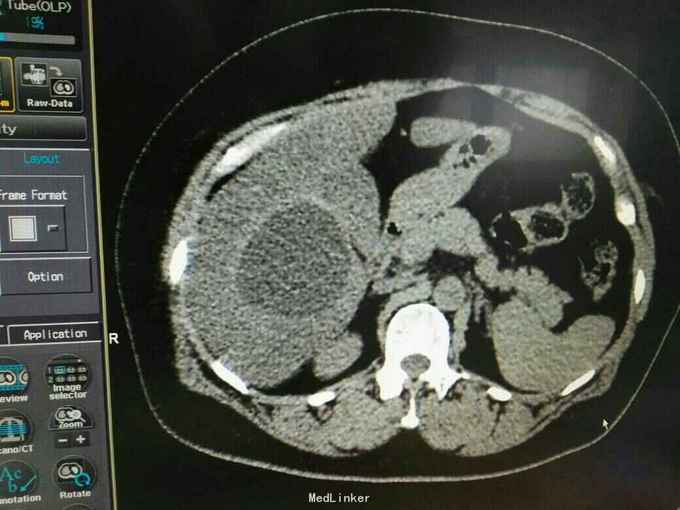

巨大肝囊肿

【原创】巨大肝囊肿图片,与各位分享